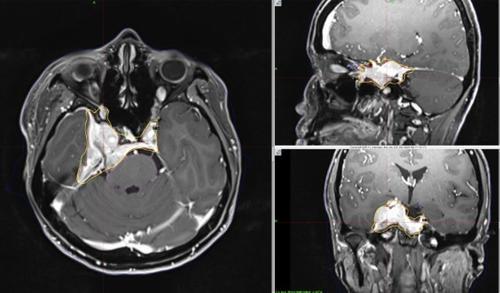

■病例1

38岁的娜娜是一位嫁到大马的泰国女子,她因为右眼视野出现大片黑蒙和复视,做了脑部扫描,发现右颅底有一颗大肿瘤,压制视神经线、脑下垂体和脑干,经详细检查后,证实是右内侧蝶骨翼脑膜瘤(right medial third sphenoid wing meningioma)。

这是一颗良性瘤,但却有3.6x3.5x2.5公分大,对视觉造成重大影响,必须及早治疗。肿瘤长在神经交叉处,周遭血管密布,位置也很贴近脑下垂体,想要彻底切除是不可能的任务。

但当务之急还是先开刀,切除部分肿瘤,及时为视神经线减压,拯救娜娜的视觉。术后,娜娜的视野比较明亮了,化验报告也证实是第一级脑膜瘤。

5天分次放射 稳控残余肿瘤

盛医生和肿瘤科医生讨论后,认为复发的可能性颇高,像娜娜这种已开颅切除部分肿瘤,却仍有肿瘤残留的病患,伽玛刀是一个很好的后备治疗方法。

由于残留的肿瘤体积超过3公分,他于是把伽玛刀治疗分成5个疗程,连续5天进行,每次给予5Gy的剂量。这是伽玛刀的最新技术,能够执行分次的放射手术,治疗大体积的肿瘤。

伽玛刀放射手术由脑神经外科和肿瘤科一起执行,治疗前,先用MRI和电脑断层扫描(CT scan),配合立体定位技术,精确标记肿瘤的三度空间座标,再利用面罩,把娜娜的头颅依座标值固定,确保放射线准确聚焦。